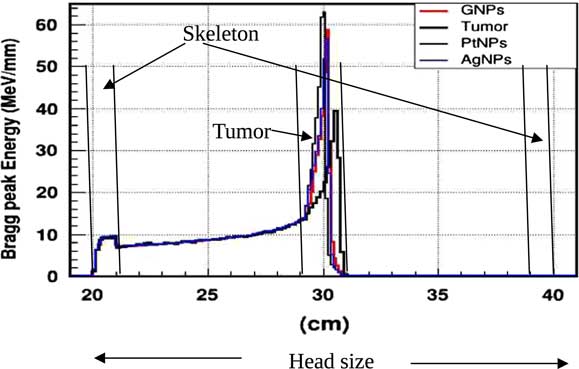

In practice, proton therapy can be used in two ways known as passive scattering and pencil beam. The first technique is based on a single scattering foil (made out of lead) used to broaden the beam. In the second technique, the proton beam is deflected with a magnetic field to generate a narrow monoenergetic pencil beam and scan it magnetically across the tumour. Both of these techniques should be used carefully. Our principal goal is to investigate on how NMs affect on proton therapy. The deposited energy along the head is plotted in the Figure 4. This plot is obtained from a Monte Carlo simulation of 106 protons beam energy of 125 MeV. This figure shows that NMs enhance in a significant way the deposited energy in the tumour. Furthermore, the platinum NPs (PtNPs) present the more efficiency. In order to investigate deeply the enhancing proton therapy by NMs in tumour, we have plotted the deposited energy only along the tumour ranging between 29·2 and 30·8 cm.

Figure 4 The deposited energy of a monoenergetic proton beam along a head. Notes: The Bragg peak energy issued from 106 protons placed at 1 m from the head. The proton beam energy is 125 MeV. Abbreviations: GNPs, gold nanoparticles; PtNPs, platinum nanoparticles; AgNPs, silver nanoparticles.